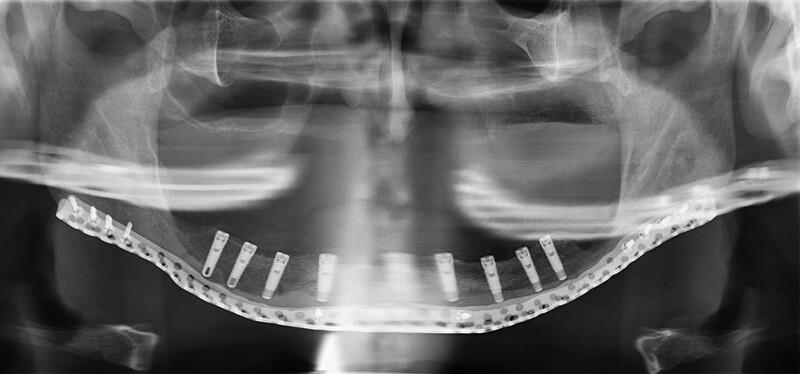

Patient-specific Implants for Treating Atrophic Mandibles.

Extremely atrophic mandibles are difficult to treat. Most patients choose to live with removable dentures. However, what if the atrophy is so extreme that spontaneous fractures occur? The objective of this report is to offer a single-stage augmentation method, which uses patient-specific crib-shaped implants (PSI) combined with autogenous free bone grafts. PSI were planned using three-dimensional (3D) segmentation and 3D virtual-planning software. Implants were designed according to the patient's mandible with a mesh-like structure and included large holes for allowing blood supply recovery. During surgery, the PSI fitted perfectly. In cases exhibiting malposition of the mandibular fragments, repositioning was performed using 3D virtual planning. When repositioning mandibular segments, the PSI served as a guide for the correct positioning. Iliac-crest bone graft was harvested and fixed as an onlay over the residual mandibular basal bone. External approach was used to avoid contamination. Six months following surgery, fixation wires were removed, and dental implants were positioned in the newly formed bone. The PSI allowed for rigid fixation, thus leading to optimal incorporation of the iliac-crest bone graft. No further augmentation was required. Bony continuity for future stability and secession of the spontaneous fractures was achieved. Dental implants were placed effortlessly. Treating extremely atrophic mandibles is an entity of its own and is considered one of the most challenging in craniofacial reconstruction. It mostly requires multiple operations with high rates of failure. We offer a novel method of 3D mandibular reconstruction, both vertically and horizontally, showing promising results and achieving enough bone for further dental rehabilitation.